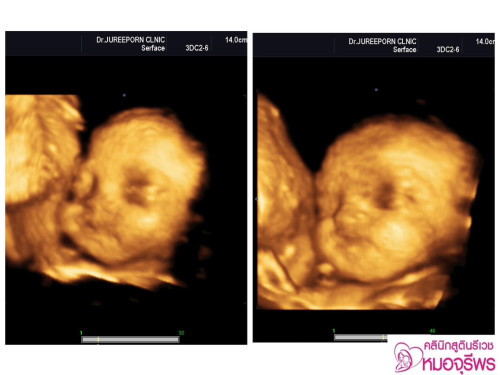

พอดีเราครบ 29 สัปดาห์ ไปอัลตราซาวด์มา น้องน้ำหนักแค่ 777 กรัมอยู่เลยค่ะ